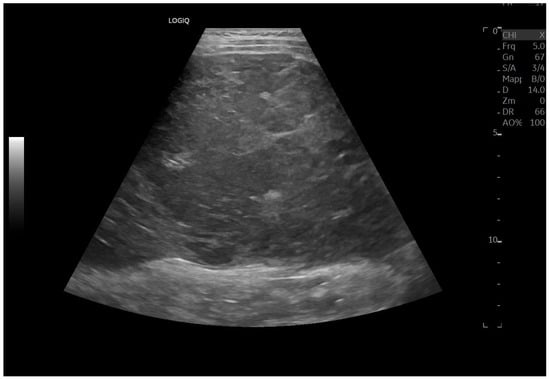

A cohort analysis involving 55 individuals who had undergone the Fontan procedure demonstrated that 67% displayed irregular hepatic echotexture or surface nodularity, changes that showed a temporal association with the duration since surgery. Severe congestion with PHTN may present with dilated portal veins (diameter > 13 mm), enlarged paraumbilical veins, collateral circulation, splenomegaly (Figure 9), ascites, and reversal of portal vein flow [50,52,53].

Figure 9.

Splenomegaly: bipolar diameter 16 cm (normal value: 12 cm); sectional area 81 cm2 (normal value: 45 cm2).

Compared to liver cirrhosis from other causes, extrahepatic portosystemic collaterals in FALD tend to be infrequent or of limited size, even when liver disease becomes decompensated. This occurs because the Fontan circulation generates markedly elevated systemic venous pressures while maintaining only a minimal gradient between the portal and systemic venous systems, conditions that hinder the development of substantial portosystemic collateral pathways [54]. Doppler ultrasonography represents the most informative imaging modality for evaluating liver involvement. It provides detailed information on blood flow and supports the assessment of portal hypertension as well as secondary findings such as splenomegaly, hepatomegaly, ascites, and hepatic nodules [55].